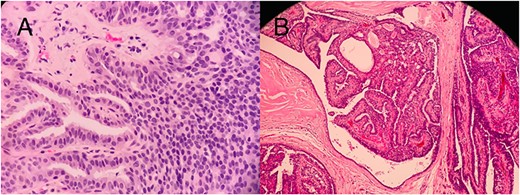

Histopathology slides (A) CNB showing papilloma lined by a double-layer epithelium with foci of ADH without invasion. (B) Postmastectomy, showing a solid DCIS.

Five months later, she returned for medical treatment, and US follow-up revealed some changes in the two most suspicious lesions; one of them had become longitudinally oriented with posterior acoustic shadowing, irregular infiltrating serrated borders, and tiny microcalcifications inside. The other lesion was mildly enlarged with microlobulated outer borders (Fig. 4). Typical malignant US features were found; so the outer lesion was upgraded to a BI-RADS V classification (Fig. 4). A decision was made to repeat the biopsy, which showed ADH with no infiltrating malignancy (Fig. 5). The patient was counseled regarding her diagnoses and the proposed management plan, which was open excision of the two highly suspicious lesions, yet she insisted on having a right simple mastectomy. The risks and possible postoperative complications of the chosen type of operation were explained to her and her family, and they agreed to proceed. Due to the high malignant potential of right breast lesions and the patient’s desire for simple mastectomy, a right simple mastectomy with sentinel lymph nodes biopsy was performed.

The postoperative histopathology report showed the spread of right breast DCIS and microcalcifications through all breast quadrants (Fig. 5). Unintentionally, seven axillary sentinel lymph nodes, which were matted and aggregated together, were found to be reactive without any evidence of malignancy. The patient was reassessed at 2 weeks and at the 1- and 2-year follow-up visits and was found to have no evidence of any local recurrence in the right mastectomy scar.